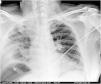

A 49-year-old male presented with no medical history apart from laparoscopic right renal cyst (Bosniak III-IV) removal performed a month ago. He presented to the emergency room with malaise, nonspecific abdominal pain and dyspnea. The initial chest radiographic study (Fig. 1) suggested pneumoperitoneum. The subsequent abdominal CAT scan (Fig. 2) revealed a subphrenic collection with an air-fluid level. Surgery confirmed retroperitoneal right colon perforation. Although retroperitoneal colon perforation is usually associated with retropneumoperitoneum and retroperitoneal abscesses, neither of these conditions were observed in the present case. The patient exclusively presented a subphrenic abscess with an air-fluid level, which additionally produced a false image of pneumoperitoneum on the chest x-ray examination.